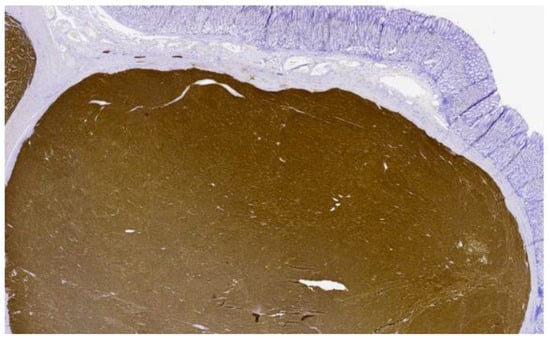

Pathology was consistent with a multifocal, invasive, gastric and duodenal GIST with a predominant spindle cell component (Figure 2 and Figure 3). The size sample could not be measured with accuracy, but it was more than 5 cm. The mitotic index was <5 mitosis/5 mm2. Immunohistochemical studies were highly positive and diffuse for CD117. Surgical margins were positive, and there was a lymphovascular invasion. Metastasis was found in 5 of the 11 excised lymph nodes, including 2 lymph nodes localized on the greater omentum. The tumor was classified as a pT3(m)N1 according to the AJCC Cancer Staging Manual 8th edition. Molecular studies were negative for KIT and PDGFRA mutations.

Figure 2. Pathological cut of gastric GIST with immunohistochemistry stain for CD117/c-kit.